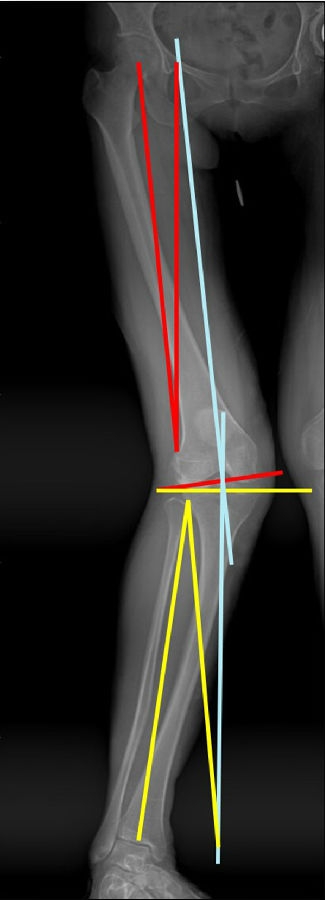

患者二,女性,膝外翻,膝外侧疼痛。通过做畸形分析后发现,该患者同时存在股骨侧畸形、胫骨侧畸形和关节内畸形(LDFA=82°,MPTA=104°,JLCA=6°)。

对于这类病人如何进行术前设计的关键点就在于目标力线应如何设计。要在骨性截骨的时候纠正骨性畸形,关节内畸形要通过关节内的方法解决。因为JLCA不平行,所以要同时画股骨侧关节线和胫骨侧关节线,并垂直于股骨侧关节线做出股骨侧目标力线,垂直于胫骨侧关节线做出胫骨侧目标力线。

根据各自目标力线,分别计算股骨内侧闭合和胫骨内侧闭合角度。

此患者股骨内侧闭合6°,经股内侧闭合13°。